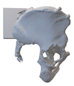

Therefore, the aiming device was first validated on a virtual 3D model. The entry and exit points and the path it takes through the bone were clearly visible in the design software, using the semi-transparent display mode. Then, the 3D-printed targeting model was fitted to the previously printed hemipelvis with its actual dimensions. The accuracy of the aiming was also verified by test drilling. The assembled model was then available to the surgeon in the OR for visual inspection, which helped to ensure spatial orientation (Figure 3).

Figure 3.

The 3D-printed hemipelvis with the aiming device in the OR.